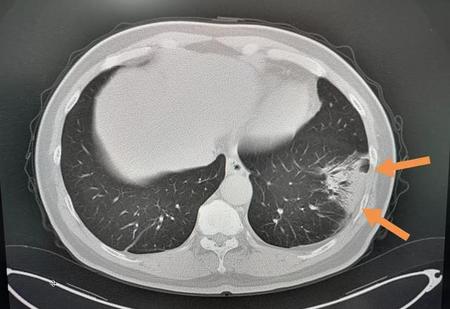

这位中年男子,咳嗽发热三天,CT发现左下肺炎,沿亚段分布,密度比较高(不是磨玻璃影),肺门侧可见支气管充气征,伴有血象增高,这就是个普通肺炎,不是冠状病毒。

经抗生素治疗,9天后明显吸收,目前已经出院了: